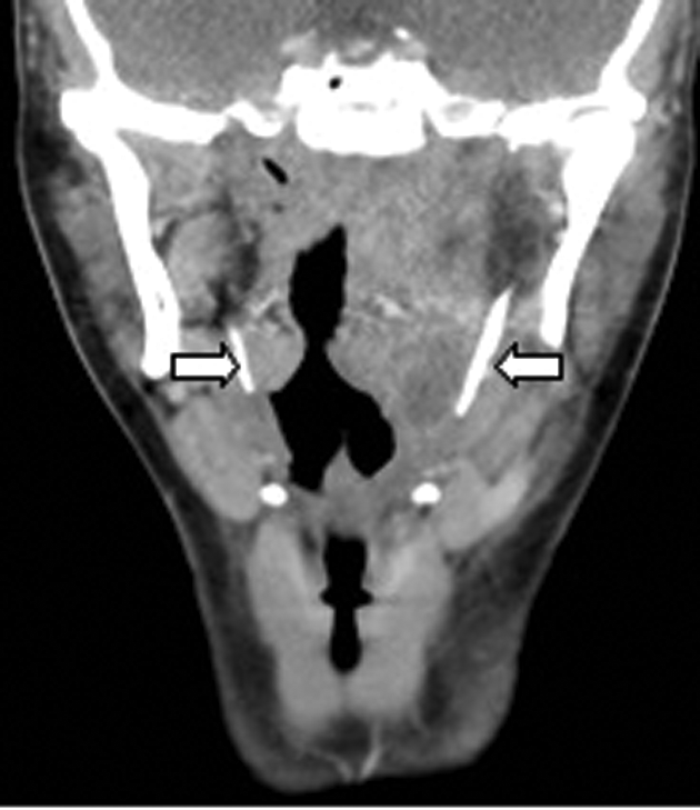

CT (Figure 8) demonstrated a left peritonsillar abscess. In addition Figure 9 shows the patient to have bilateral calcified stylohyoid ligaments. Pharyngitis / tonsillitis are common causes of referred otalgia. Additionally calcification of the stylohyoid ligament greater than 28mm can compress the glossopharyngeal nerve causing dysphagia, tinnitus and otalgia, a collection of symptoms termed as Eagle’s Syndrome.

Figure 8: Contrast enhanced CT demonstrating a left peritonsillar abscess (white arrow).

Figure 9: Coronal contrast enhanced CT of the same patient demonstrating

bilateral calcified stylohoid ligaments (white arrows).